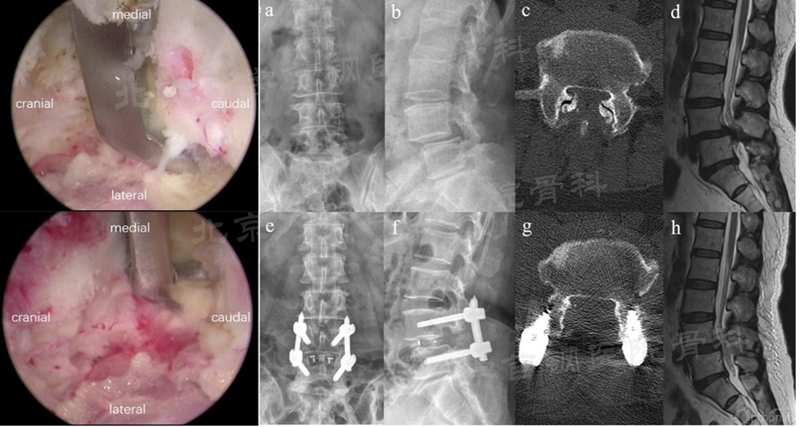

(5)双侧双cage融合术:该术式除了植入双cage的优势外,还可以借助Zhang切口对对侧进行高效率的减压,同时可以切除对侧关节突关节以实现滑脱更好的复位(如图26)。

图26 利用Zhang切口可以高效处理对侧减压,切除对侧小关节实现滑脱复位(图片来源于文献)

(6)双侧双cage融合术刚由张伟教授团队报道出来,但通过展示的病例来看,其对于腰椎滑脱具有较好的优势,但据笔者所知,此手术方式病例数较少,尚无临床结果报道,目前未见有其他学者应用,相信未来会有更多应用结果被报道出来。